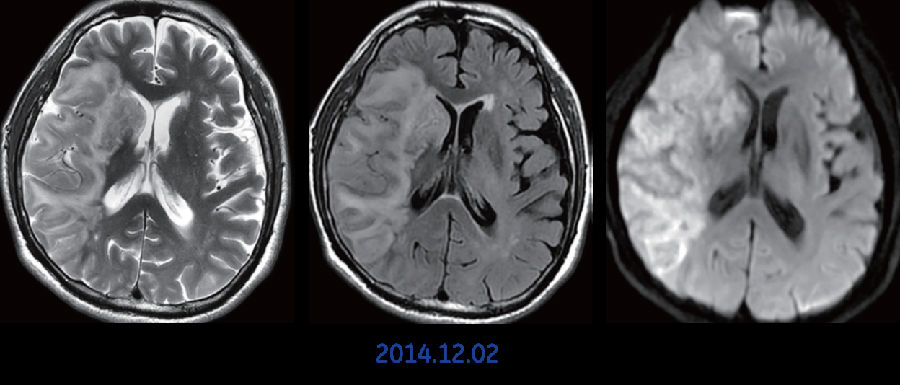

扫描序列: 弥散,T2wI,3D ASL, T2 FLAIR

影像分析: 该患者初始检查时怀疑超早期脑梗塞,并且在两周后进行复查。 首次检查时,该患者进行了常规的T2wI,DWI,以及3D ASL扫描。T2像时病灶显示不明显,但弥散图像上右颞叶见弥散受限病变,提示早期脑梗塞。同一时间,进行3D ASL灌注成像,图像显示右侧额、颞、顶叶大片灌注减低区,弥散与灌注严重不匹配,提示半暗带存在。半暗带即提示存在那种可以挽救的脑组织区域,但同时也预示这部分脑组织有可能转变为不可逆梗死,在评判预后应予以足够重视。 两周后复查,进行T2WI, T2 FLAIR, DWI扫描。弥散图像上右颞叶见大面积弥散受限区域,并且与首次检查时3D ASL所提示的大面积低灌注区域高度一致。复查时该区域已经转化为大面积脑梗塞。

最后诊断: 右大脑半球大面积脑梗塞

技术点评: 弥散成像能敏感发现急性或超急性期脑梗塞,而3D ASL灌注成像则较弥散更为敏感提示缺血存在,在评判预后时结合3D ASL灌注成像能更客观、准确地评判预后。